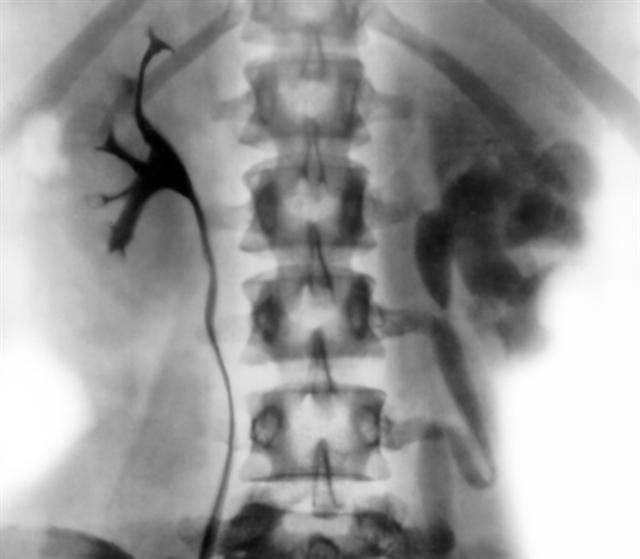

Рис. 9а. Экскреторная урограмма при фиброзно-кавернозном туберкулезе левой почки и туберкулезе левого мочеточника: выраженные ретенционные изменения чашечно-лоханочной системы левой почки и левого мочеточника, верхние почечные чашки не заполнены рентгеноконтрастным веществом. |